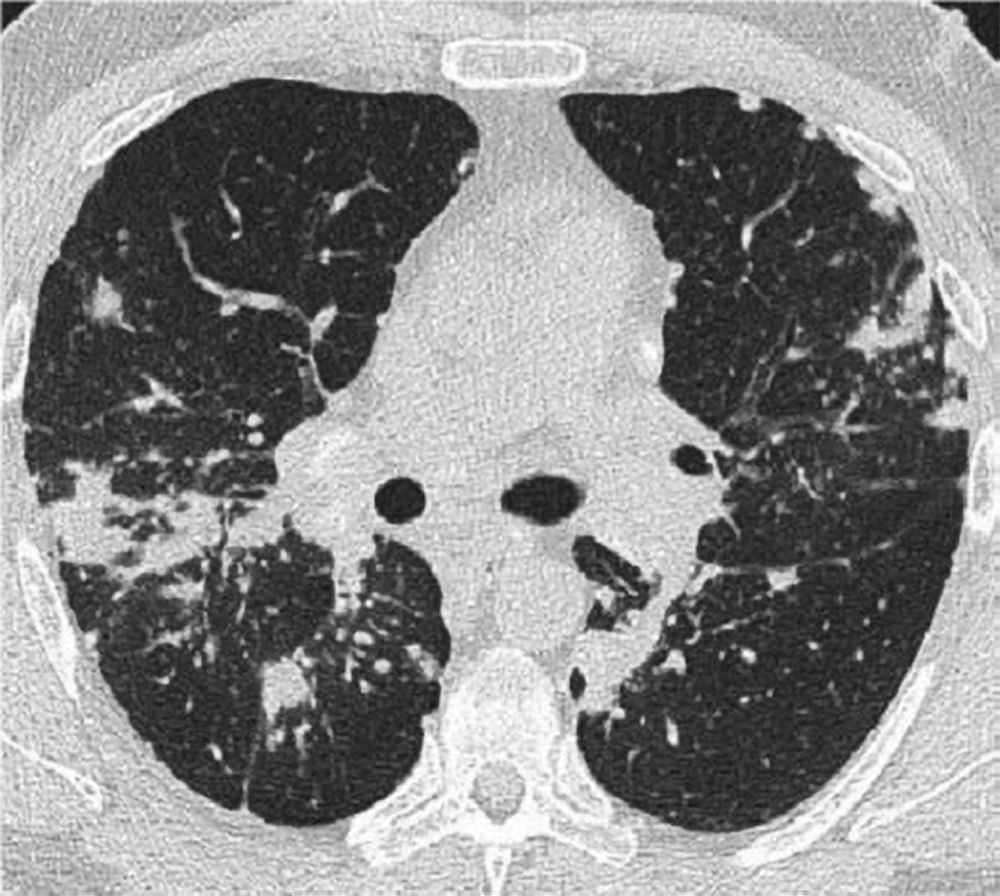

La radiografia del torace (RX) rimane il punto di partenza per la classificazione della sarcoidosi polmonare, utilizzando il sistema di Scadding che divide la malattia in quattro stadi principali sulla base dei reperti linfo-parenchimali.[1, 12, 13]

Tuttavia, la TC ad alta risoluzione (HRCT) è oggi considerata indispensabile per una migliore caratterizzazione. I segni tipici alla HRCT includono noduli a distribuzione perilinfatica (lungo i setti interlobulari e le scissure), ispessimento dei fasci broncovascolari e opacità a “vetro smerigliato” che riflettono un’alveolite granulomatosa attiva.